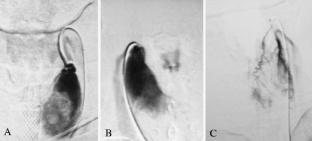

Fig. 1